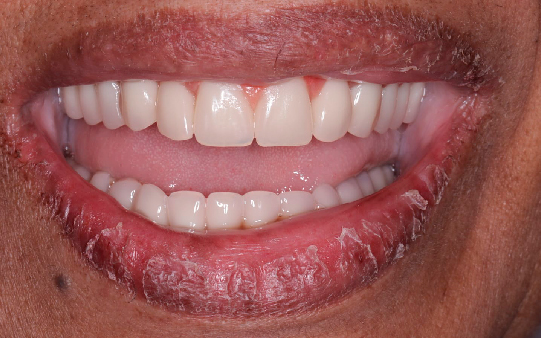

Protocolo em Resina Acrílica: boa estética, acessível, indicado para reabilitações com ótimo custo-benefício.

Esse é o momento perfeito para você trazer o seu sorriso de volta!